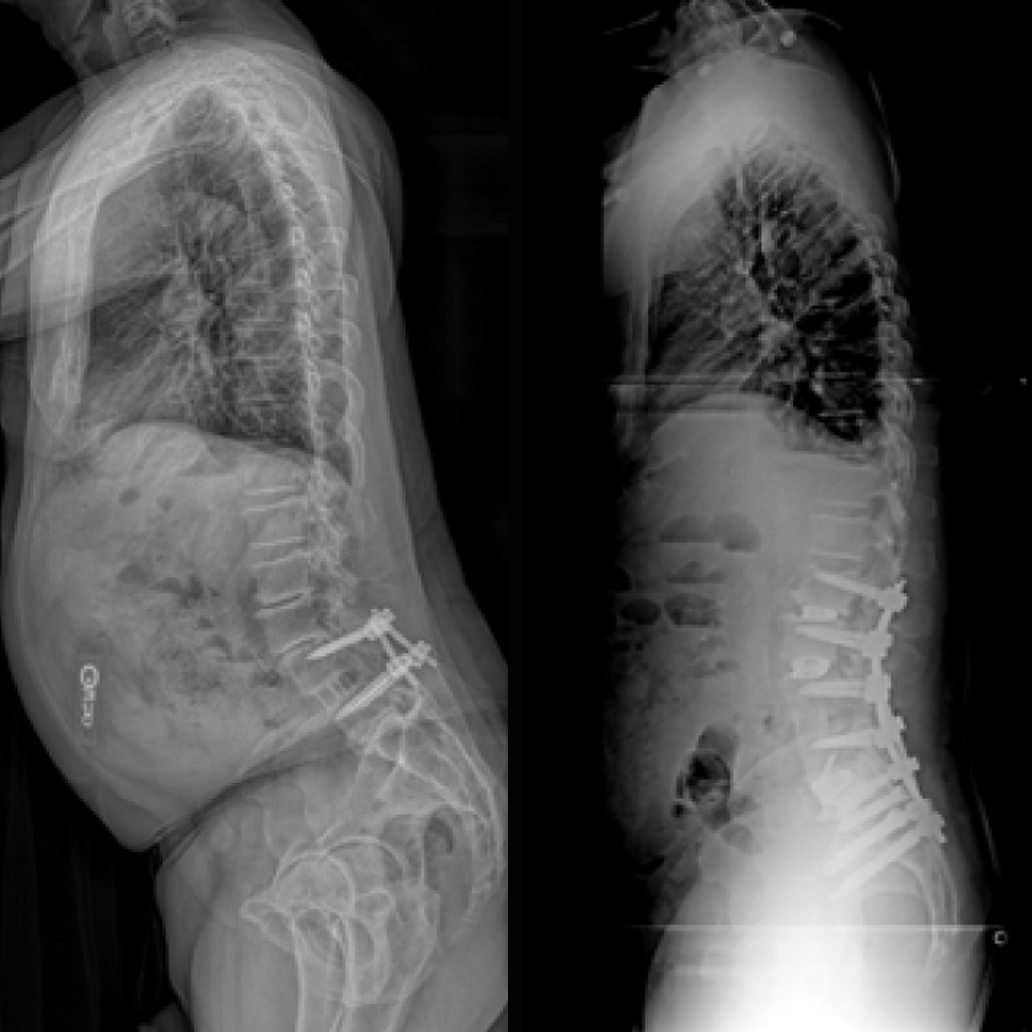

Sagittal Plane Deformity

Patient History:

- 77 y/o male physician with chronic LBP > leg pain

- Difficulty standing/walking, fatigues quickly

- Forward posture

- Positive thigh trust, FABER, Gaenslen’s

- Failed non-surgical management

- LLIF/open PSF L4-5 > 10 years prior

Surgical Treatment:

- ALIF L5-S1 with LLIF L2-4 in single lateral position

- L2-pelvis fusion with MIS S2AI iFuse Bedrock Granite™ and iFuse TORQ™ for bilateral SAI spinopelvic stabilization and SI joint fusion

Post-op:1,2

- Marked pain relief and normalized posture at 6-month post-op

- Walking 4-5 miles

- Anxious to return to pickle ball